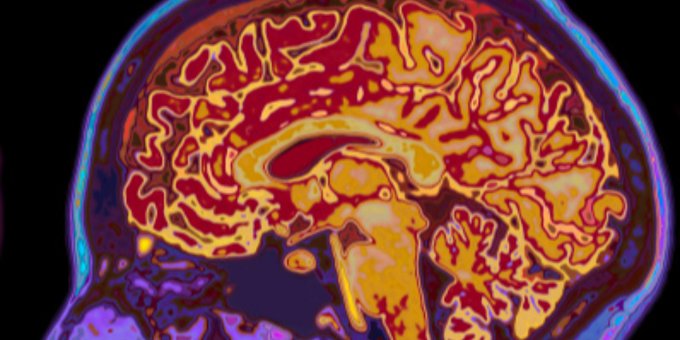

Un ataque isquémico transitorio es un derrame que dura apenas unos minutos. Esto ocurre cuando el suministro de sangre a una parte del cerebro se detiene brevemente. Más aquí ow.ly/5rkO50yf8JH